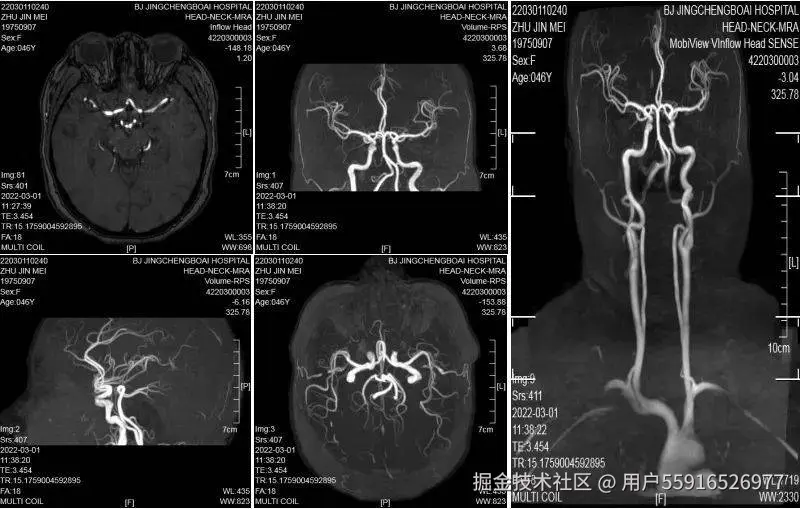

脑部核磁共振功能较多,“一站式”可分为不同的扫描序列和成像,包括头部核磁平扫(MRI)、脑血管成像(MRA)、弥散成像(DWI)、磁敏感成像(SWI)。MRI可查看颅内是否有脑肿瘤、脑梗塞、发育畸形等疾病;MRA可用来发现颅内动脉瘤、动静脉畸形等血管疾病;DWI常用来判断是否发生急性脑缺血;SWI对微小静脉出血诊断敏感。我院影像科可以通过一次扫描完成脑内占位、血管疾病、脑梗的检查,为临床提供较为全面的诊断依据。

老年人是高血压、高血脂、糖尿病的高发人群,随着年龄增加,脑动脉硬化、狭窄、脑动脉瘤等发生率增加,而早期脑血管改变不会引起明显的特异症状,容易忽视,一旦发生脑卒中(脑梗塞或出血),后果严重。“一站式”脑部核磁共振检查可以早期发现是否有脑动脉瘤,也可以发现脑动脉是否硬化和狭窄。尽量做到早发现、早干预,从而有效降低脑卒中的发生。